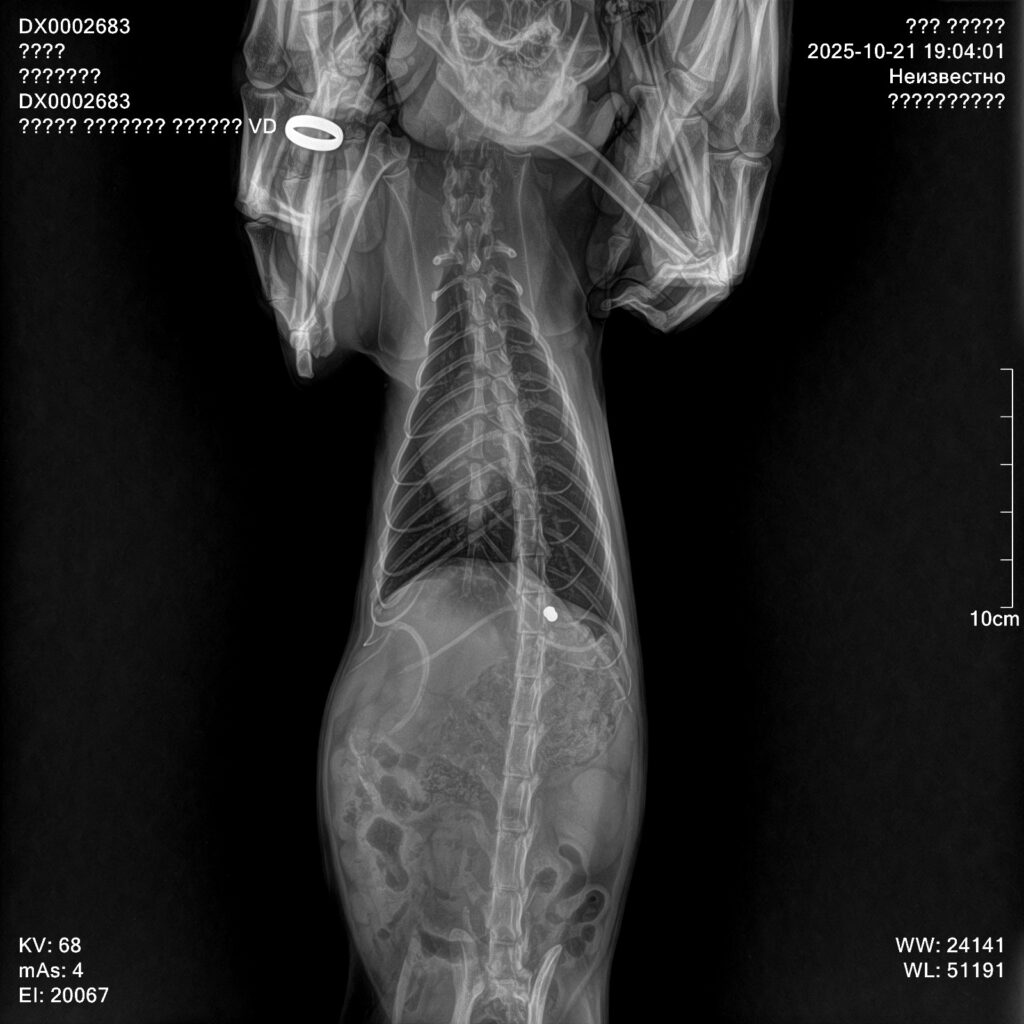

Дома волонтер ощупала животное и ужаснулась. Под шерстью «гуляли» острые ребра. Неля вместе с супругом повезли его к ветеринару. В клинике врачи сделали рентген, который показал, что сломаны четыре ребра, а еще маленькую пулю в печени. Получается, в кота кто-то стрелял.

«Пока непонятно, где это произошло и сколько он так ходил. У него уже начался отит, блошиная инвазия. Проблемы с почками и печенью. Сделали два УЗИ. Состояние среднее. Но он держится», — говорит Неля.

Теперь трехлетнему коту, которого назвали Майком, предстоит операция. Придется удалять поврежденные ребра. Если их не убрать, обломки могут проткнуть внутренние органы. Также извлекут пулю. Перед манипуляцией в клинике он проведет пять дней. У него возьмут анализы и сделают полную обработку.